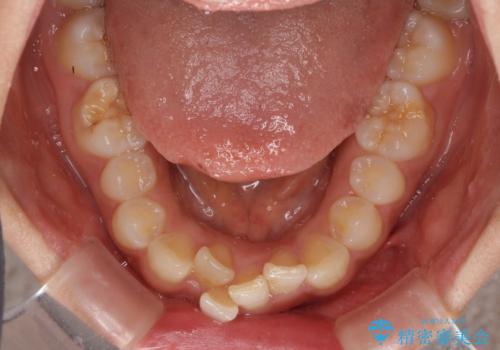

- 飛び出した前歯と全体的なデコボコを気にして来院された患者様です。

上下歯列全体を後方に移動させるため、親知らずは全て抜歯することにしました。

大きなトラブルもなく、順調に歯列が整ったため、僅か9ヶ月で装置を外すことができました。